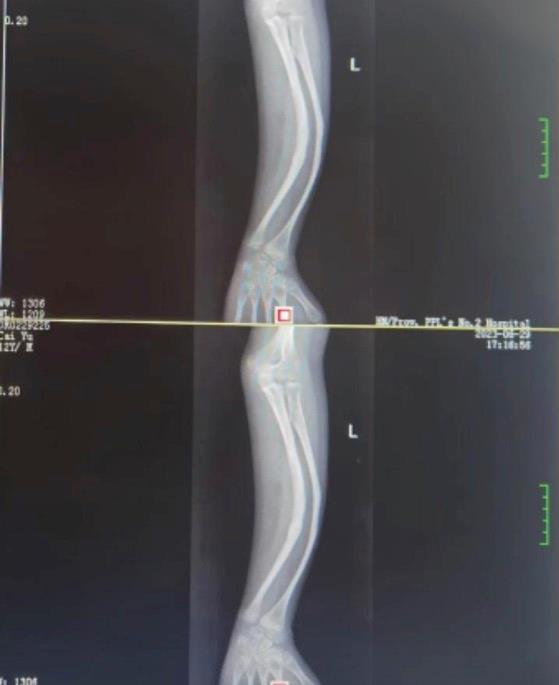

少年骨折后感染致慢性骨髓炎手臂成弧形,3D打印幫助一次完成4個手術

蔡同學 9 歲時因左臂骨折手術后感染導致慢性骨髓炎,且畸形日漸嚴重。" 手臂都彎成了弧形,嚴重影響生活和學習,導致孩子有點自卑,再加上怕孩子長大后更難治療。" 小蔡的媽媽說。這些年,他們求醫心切,輾轉多家醫院進行治療。

△術前影像

由于小蔡同學左前臂嚴重畸形,同時存在大角度的內翻、前凸畸形,加上長時間的骨髓炎導致彎曲部位的骨組織硬化、髓腔消失,術后面臨矯正不充分、斷端不愈合或再次感染的風險。

如何做到討論充分、論證嚴密、評估準確、方案明晰、風險可控,付三清利用先進的 3D 打印技術,定制患者 1:1 大小實體畸形骨骼模型,針對手術方式、截骨部位、截骨角度、固定材料選擇等進行詳細手術方案論證、手術模擬,并根據手術綜合因素考量制定了詳細截骨矯形方案,并通過術前定制導板確保術中截骨準確。

由于前期對 3D 骨骼模型進行了多次模擬操作,當天手術完成得非常順利。付三清教授帶領手術團隊在術中一次完成尺骨楔形截骨術、橈骨楔形截骨術、尺骨內固定術、橈骨內固定術等手術。

術后艾緣教授指導蔡同學進行功能鍛煉,并在醫護團隊的精心照顧下,蔡同學左前臂畸形基本消失,腕、肘關節活動無阻礙,前臂旋轉活動恢復,手臂功能也得到了明顯改善。

△術后恢復情況